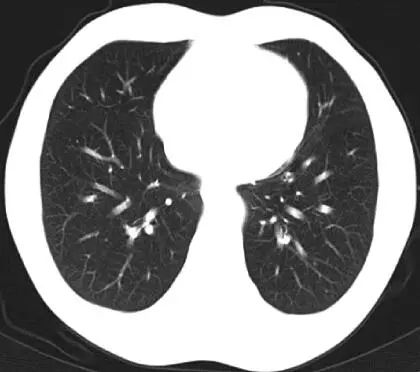

(2) 治疗予紫杉醇+顺铂+贝伐单抗治疗4 个周期后,肺部CT(图4):未见转移病灶。复查肝脏及盆腔MRI(图5):肝脏S2、S6 病灶消失,S4 病灶较前明显缩小。

图4 4个周期化疗+靶向治疗后肺部CT检查结果